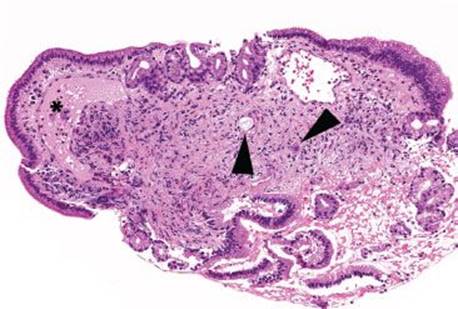

Figure 3.313 Acute duodenitis with gastric foveolar metaplasia and reactive epithelial change. The clinical impression of a mass lesion inspired deeper sections on this busy-appearing biopsy, although no histologic features of malignancy are readily apparent on this first level.

This case was received as “prominent ampulla, concerning for malignancy” (Fig. 3.313). The initial sections show duodenal mucosa with acute and chronic inflammation, gastric foveolar metaplasia, and marked reactive epithelial change (Fig. 3.313). Although these histologic features can account for a nodular clinical impression, deeper sections were pursued based on the clinical suspicion for malignancy. The first set of deeper sections were similarly concerning, but definitive malignancy was not seen. Deeper sections were repeated. And repeated. And repeated. In this case, the tissue block was exhausted and on the 38th level (!!!), clear lymphovascular invasion and infiltrating adenocarcinoma were seen (Figs. 3.314 and 3.315). When the histology does not fit the clinical scenario, consider deeper sections. When the deeper sections are not conclusive, consider repeat deeper sections or recommend rebiopsy (in this case, the patient was too unstable for a subsequent biopsy).

Figure 3.314 Infiltrating poorly-differentiated adenocarcinoma and lymphovascular space invasion. Deeper sections were performed until the block was exhausted. This photomicrograph represents the 38th (and final) section, which shows desmoplasia, infiltrating adenocarcinoma (arrowheads), and lymphovascular space invasion (asterisk). These deeper sections show an entirely different biopsy compared to the initial sections and were sufficient for chemotherapy initiation.